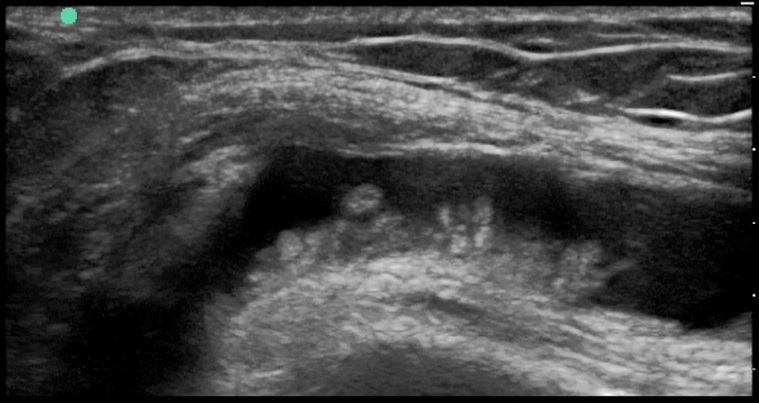

Knee Suprapatellar Pannus Image